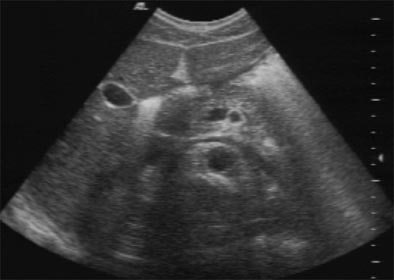

![]() |

| A transverse scan at the level of the left renal vein, captured post examination from the recorded video. In spite of degradation due to conversions, the image offers ample imaging data. |